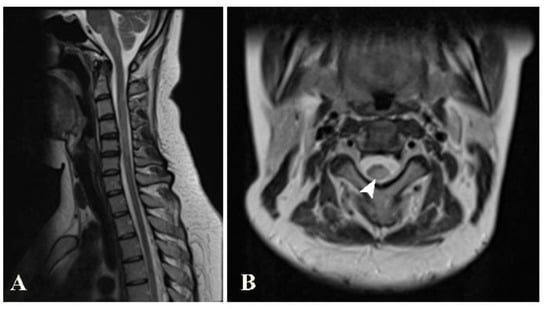

A spinal MRI was available for 26 of the patients. Of these, 23 (88.5%) showed an abnormal spinal MRI. These spinal MRIs were most frequently performed during the follow-up period (in 10 out of 26 patients, 38.5%). Almost half of the patients with abnormal MRIs showed lesions in both the cervical and the thoracic spinal cord (11 patients, 47.8%). Seven and four patients showed lesions at the cervical spinal cord only and the thoracic spinal cord only, respectively. The locations of these lesions in the axial views were most common by far in the peripheral areas (22 patients, 95.7%). Only five and two patients had lesions in the central spinal cord and whole-cross-sectional cord involvement, respectively. Regarding the spinal cord column involvement in the peripheral lesions, the most commonly involved column was the lateral column (19 patients, 82.6%), followed by the posterior and the anterior column (ten and seven patients, respectively) (Figure 7). The lesions were mainly round/oval (91.3%). The maximal length of the longest lesion, classified into shorter than three and at least three vertebral segments, showed that the predominant lesion length was shorter than three vertebral segments (15 patients, 65.2%). The median and mean lesion length were about 2 and 2.2 vertebral segments, respectively. Most of the patients showed only one or two spinal lesions (16 patients, 69.6%), with only two of the patients developing more than five lesions (8.7%). The presence of spinal gadolinium-enhancing lesions was noted in 14 patients (60.9%), with one or two enhancing lesion(s) found in each. The most common enhancing pattern was nodular enhancement (39.1%), while incomplete ring enhancement was also noted in the spinal cord in two patients (8.7%). A visual assessment found spinal-cord atrophy in four patients (12.5%; Table 3).

Figure 7.

Sagittal T2W image (A) of the cervical spine shows brainstem and several spinal cord lesions. Axial T2W image (B) shows lesions involving both central and peripheral regions of the spinal cord (arrowhead), mainly in lateral and posterior columns.

This study showed some similarities with previous studies conducted in Thailand [13]. Firstly, similar age groups and a high female-to-male ratio were noted in both studies. Regarding the MRIs, we also found that the periventricular region was the most common lesion location (78.1% in our study and 52.8% in Jitpratoom’s study). Jitpratoom et al. [13] also found that the juxtacortical region was the second most common location. Regarding the spinal MRI, Jitpratoom found that the mean length of the spinal cord lesions was 1.29 vertebral segments, whereas our study showed a mean spinal cord lesion length of about 2.2 vertebral segments [13]. Another study performed in Thailand [12] showed negative spinal MRIs in 41.9% of all the patients, with the remaining patients with positive MRIs showing cervical and thoracic spinal cord lesion in 48.4 and 29.0%, respectively. Our study showed a much higher proportion of positive MRIs (23 out of 26 patients with available spinal MRIs, 88.5%). The performance of spinal MRIs on patients with suspected spinal lesions only in our institute may have contributed to the high positive rate. Our study also identified that most of the patients had both cervical and thoracic spinal cord lesions (11 patients, 47.8%), with a cervical lesion alone or a thoracic lesion alone in seven and four patients, respectively. Tritrakarn et al. also collected data about optic nerves, showing optic nerve lesions in four of thirty patients, of whom three patients had lesions in the anterior half of the optic nerve [12]. Our study showed optic nerve lesions in seven of thirty-two patients. Of these, six short-segmental lesions were identified, of which four were located in the posterior half of the optic nerve.

In a previous study in Asia, Chong et al. (2006) found a mean length of spinal cord lesions of up to 3.6 ± 3.3 vertebral bodies [11], which was longer than that in our study. However, our study still showed longer spinal cord lesions compared with a study performed in a Western country [15], which showed predominant multiple short spinal cord lesions (with a median number of three lesions and a median length of 0.8 vertebral segments). Li et al. (2014) found that in the early onset of classical MS, spinal cord swelling may be shown, while in optic–spinal MS, spinal cord atrophy may be seen [10]. In our study, two patients with cord swelling and four patients with cord atrophy were found. A previous Western study observed Dawson’s fingers in 31–37 out of 40 patients (78–93%), depending on the observers [16]. A previous study, in China, showed Dawson’s finger in 59 of 80 patients (73.8%) [17]. In addition to the predominance of periventricular lesions, as mentioned above, our study also showed periventricular perpendicular lesions, or Dawson’s fingers, in as many as 20 patients (62.5%).